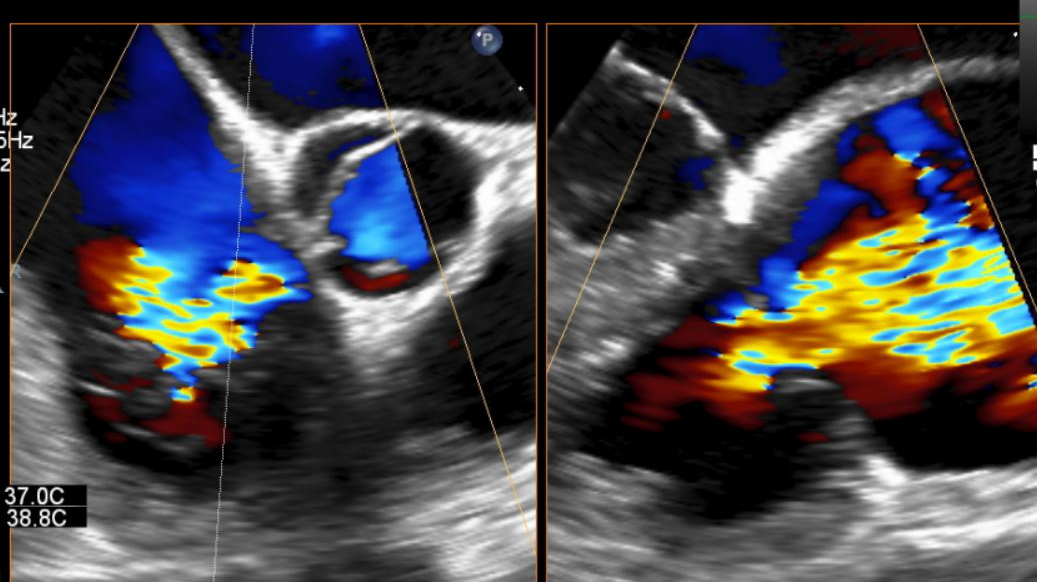

同时其夹子系统继承于申淇淇麟经导管二尖瓣缘修复系统的优秀设计,具备四个不同型号的夹子及瓣叶分开捕获能力,从而使用更加复杂多变的三尖瓣解剖。因该患者三尖瓣反流束较宽,瓣叶存在较宽的关闭裂隙,术中很好的利用了瓣叶分开捕获的功能,于前隔瓣区域行瓣膜缘对缘修复。夹子植入后,患者反流明显减轻至轻度(视频2/图3)。患者术后回复良好,出院前TTE提示轻度反流。

视频2:术后3D TEE彩色多普勒提示三尖瓣反流明显降低。